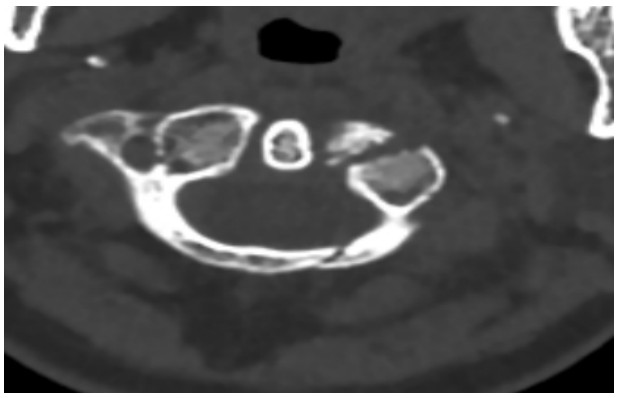

國慶節(jié)前一天,譚女士不幸被門框砸傷頸部,劇烈的疼痛和頸椎的活動受限讓她的世界瞬間陷入了黑暗。在經(jīng)歷了初步的檢查后,譚女士被診斷為寰椎骨折,這個診斷如同一道晴天霹靂,讓她和家人的心沉入了谷底。絕望中,譚女士被緊急轉(zhuǎn)至衡陽市中心醫(yī)院骨科一區(qū)(脊柱外科),錢軍博士及其團隊在接到這一緊急病例后迅速接診,經(jīng)過細(xì)致的病史詢問、體格檢查和影像學(xué)資料分析,確診譚女士的寰椎骨折伴有寰樞椎體不穩(wěn)定,迫切需要手術(shù)治療以恢復(fù)其穩(wěn)定性??紤]到上頸椎手術(shù)的高風(fēng)險性,特別是寰樞椎周圍結(jié)構(gòu)復(fù)雜,緊鄰椎動脈和脊髓,手術(shù)過程中的任何微小失誤都可能導(dǎo)致災(zāi)難性后果,錢軍博士團隊頂著壓力,迎難而上,沒有絲毫猶豫,立即行急診手術(shù),投入到緊張的救治工作中。